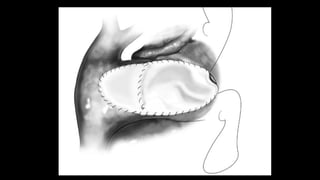

Figure 6

The

bioprosthesis

is then sewn

onto the

pulmonary

annulus

using 4-0

prolene

running

suture

Figure 7 After

completing the

suturing of the

bioprosthesis on the

posterior side, the

suture is brought

outside of the

pulmonary artery and

tied

with the suture used

in the bovine

pericardial patch for

pulmonary artery.

Figure 8 The anterior aspect of

bioprosthesis is now sewn to the

bovine pericardial patch using 4-0

prolene suture